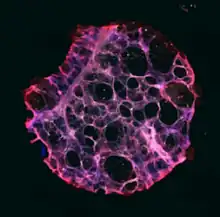

Precision-cut Lung Slices (PCLS) offer several distinct advantages that make them invaluable tools in respiratory research. They excel in preserving the intricate lung architecture, maintaining essential tissue structures like small airways, respiratory parenchyma, structural and immune cell populations, and connective tissue.[34] The cellular composition within PCLS closely mirrors that of intact lungs, retaining the organization of structural and immune cells.[35][36] However, it's important to note that specific cell types' distribution may vary among slices due to regional variability within the lung, especially in the presence of non-uniform disease-related changes.[37]

In certain contexts, PCLS can be considered as "mini" lungs.[38] While lacking a recruitable immune system, PCLS provide a unique opportunity to correlate cell-specific functions with organ physiology. They exhibit complex responses to challenges and stimuli, such as airway contraction and immune responses, shedding light on disease mechanisms and treatment evaluations.[39]